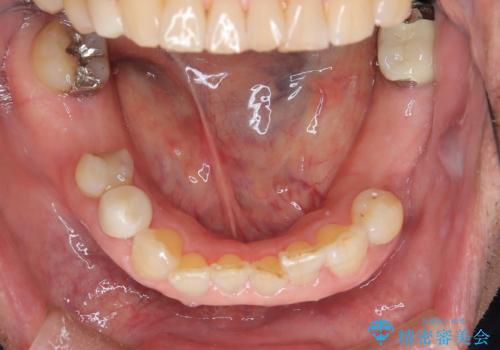

総合歯科治療

インプラント治療&セラミック治療掲載症例数197件

インプラント治療&矯正歯科治療掲載症例数37件

インプラント&根管治療&矯正歯科掲載症例数7件

根管治療&セラミック治療掲載症例数205件

根管治療&矯正歯科治療掲載症例数8件

歯周病治療&インプラント治療掲載症例数74件

歯周病治療&セラミック治療掲載症例数192件

歯周病治療&矯正歯科治療掲載症例数22件